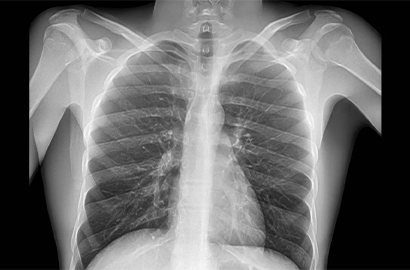

Asthma is a chronic respiratory condition that affects millions of people worldwide. It is characterized by inflammation and narrowing of the airways, leading to difficulty in breathing. At Oracle Healthcare, located in Star Green Building, Patharghata Road, Matigara, Siliguri, Dr. Sujit Gupta, our esteemed Consultant Pulmonologist, specializes in providing comprehensive asthma treatment to help you breathe easier and live a healthier life.

• Diagnosis: Dr. Sujit Gupta uses advanced diagnostic tools and techniques to accurately diagnose asthma and determine its severity. This includes spirometry tests, peak flow measurements, and allergy testing.